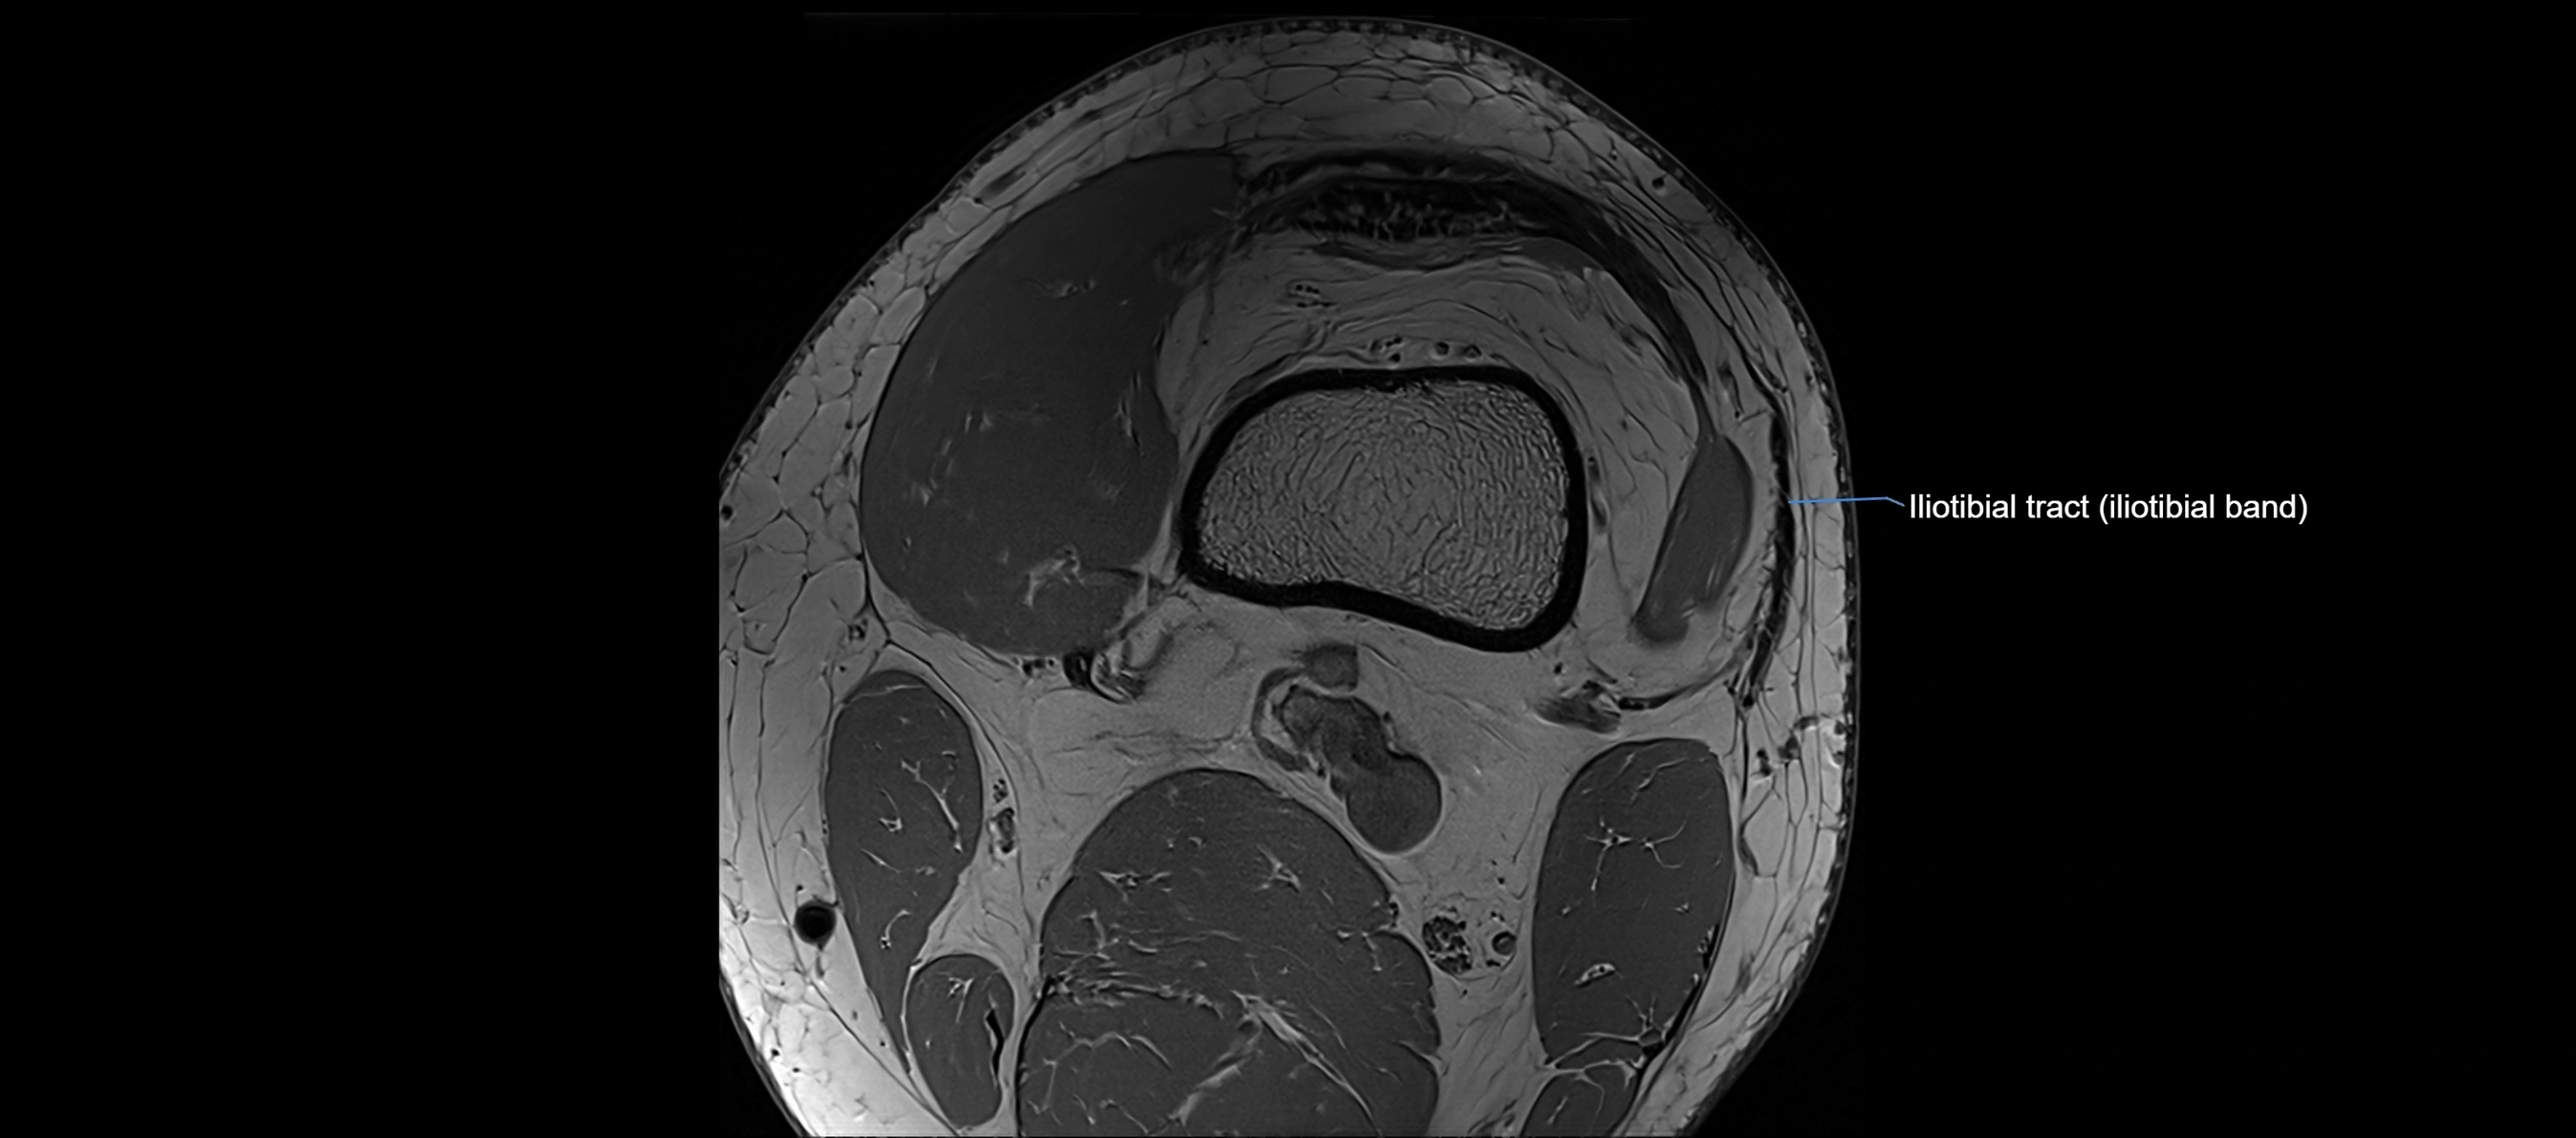

MRI Appearance

T1-weighted images:

• Normal ACL appears as a low-signal band-like structure crossing the intercondylar notch

• Surrounded by intermediate signal synovial fluid and fat planes

T2-weighted images:

• Normal ACL remains low signal

• Partial or complete tears appear as discontinuity, increased signal, or fiber laxity